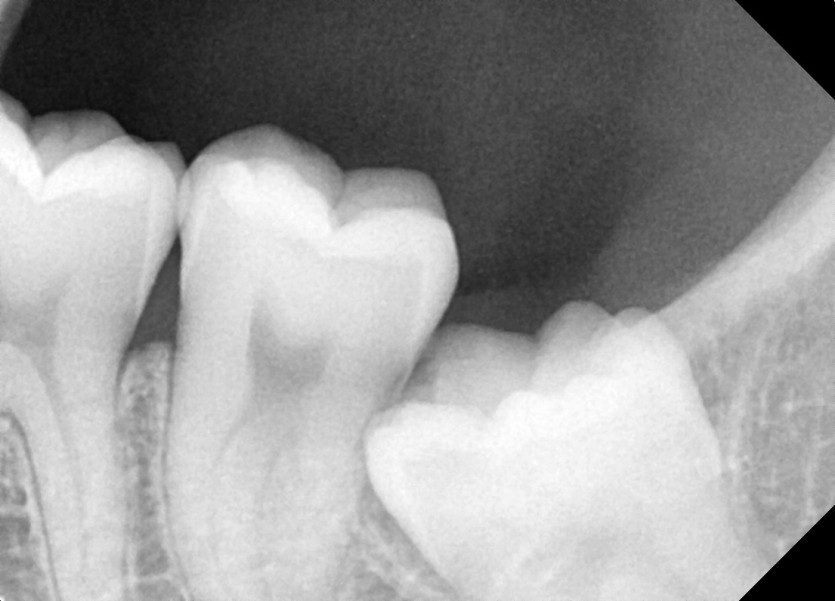

#18,28,38,48 사랑니 발치

구강 외과 전문의가 당일 발치했습니다.